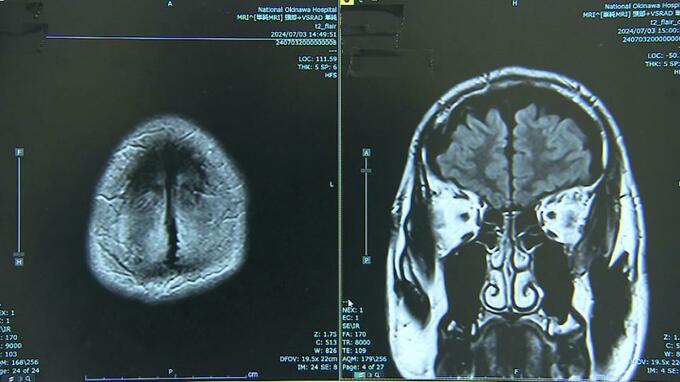

レカネマブは、2週間に1回、1時間程度の点滴治療を1年半行うほか、副作用などを確認するためMRI検査も必要で、通院が必須。